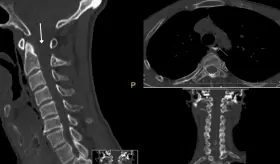

La clave estaba en entender que la tos violenta había generado una presión súbita en las arterias del cuello, causando un desgarro en la pared interna de la arteria carótida derecha.

El paciente sufrió una ruptura hipofaríngea tras un accidente de tránsito inicialmente subestimado, requiriendo reevaluación, estudios avanzados y manejo multidisciplinario conservador.